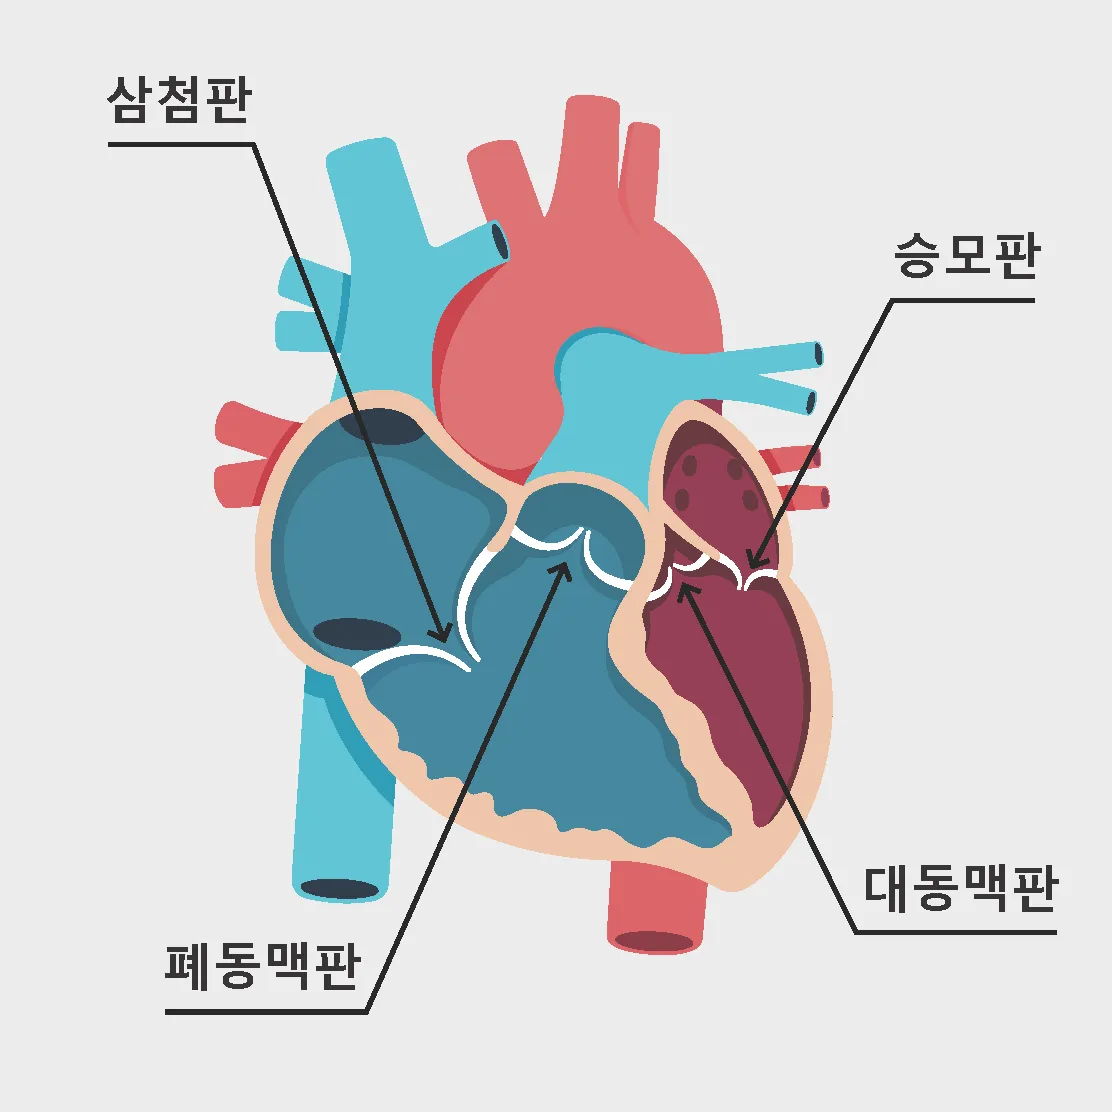

1. 심장 관련 원인

- 부정맥: 정상 심박수 범위 60-100회/분 이탈

- 심장 판막 이상: 증상 발현 시 심박수 변동 20% 이상

- 빈맥증: 휴식 시에도 심박수 100회/분 이상

- 서맥증: 심박수 60회/분 이하로 저하